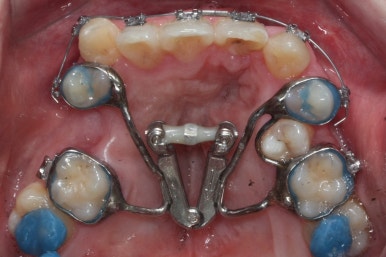

악궁확장이 시작될 시점과 악궁확장을 다 진행했을 시점의 비교입니다.

확실히 좁아져 있던 가로 넓이가 넓어진 것을 볼 수 있습니다.

악궁확장장치는 바로 제거할 경우 다시 원상태로 폭이 좁아질 수 있으므로 3~6개월은 유지해야 합니다.

위아랫니가 각각 가지런해지고 있는 것을 볼 수 있습니다.

적절한 시기가 되면 악궁확장장치를 제거하고, 확장장치가 걸려있던 치아도 가지런하게 해줍니다.